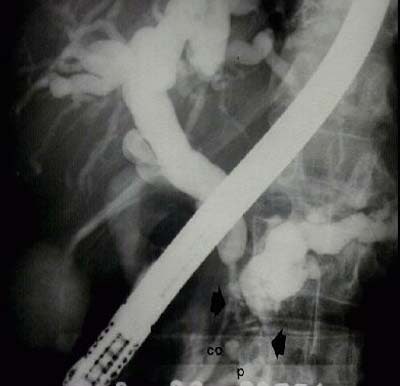

Obstruction of the common bile duct and pancreatic duct by tumoral growth at head of pancreas

A 50-year-old man who developed a greenish jaundice over 15 days, along with general decline in health, was admitted to the ultrasound department for an abdominal scan, assessment of etiology of disease, and treatment. The study showed dilatation of the intrahepatic and extrahepatic bile ducts, with distal obstruction of the common bile duct, tumor at the head of the pancreas, and dilatation of the bile duct and pancreatic duct.

![]() |

| Volumentric reconstructions obtained with 3-D ultrasound (Figure 8a, above) are compared with images obtained using endoscopic retrograde cholangeography (Figure 8b, below). Note the similarity of information that both methods bring to the diagnosis, including tumor at the head of the pancreas, and dilatation of the bile duct and pancreatic duct. |